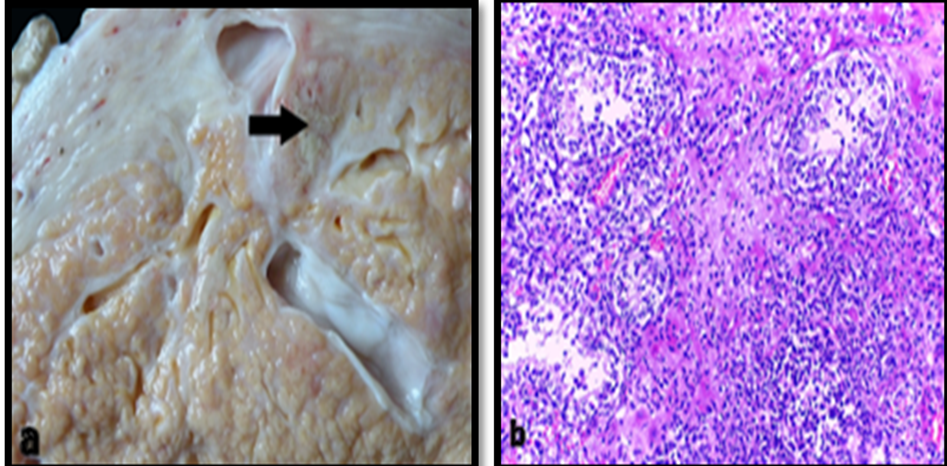

Grossly, mixed mastitis is characterized by a pronounced lobular pattern with small yellowish nodules (0.2–0.5 cm) projecting toward the ducts and cistern, interspersed with thin white septa. Histologically, there is a discrete to moderate inflammatory infiltrate of neutrophils in alveoli and ducts, with multifocal infiltration of neutrophils, lymphocytes, plasma cells, and macrophages in the interstitium (Figure 1) [37,46,47].

Figure 1. Gross (a) and histopathological (b) lesion of mixed mastitis (H&E) [37].